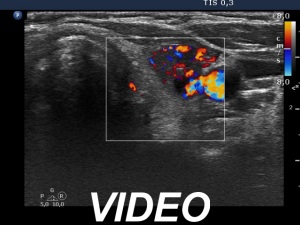

Ultrasonography. The thyroid was echonormal. There were several nodules in the left lobe. The largest in the upper pole presented all but one of the possible suspicious characteristics, it was deeply hypoechoic, had irregular margins, a microcalcification and showed abutting and bulging contours. Moreover, the intranodular vascularization was irregularly increased. One of the other lesions presented back wall figures while the third one showed taller-than-wide shape.